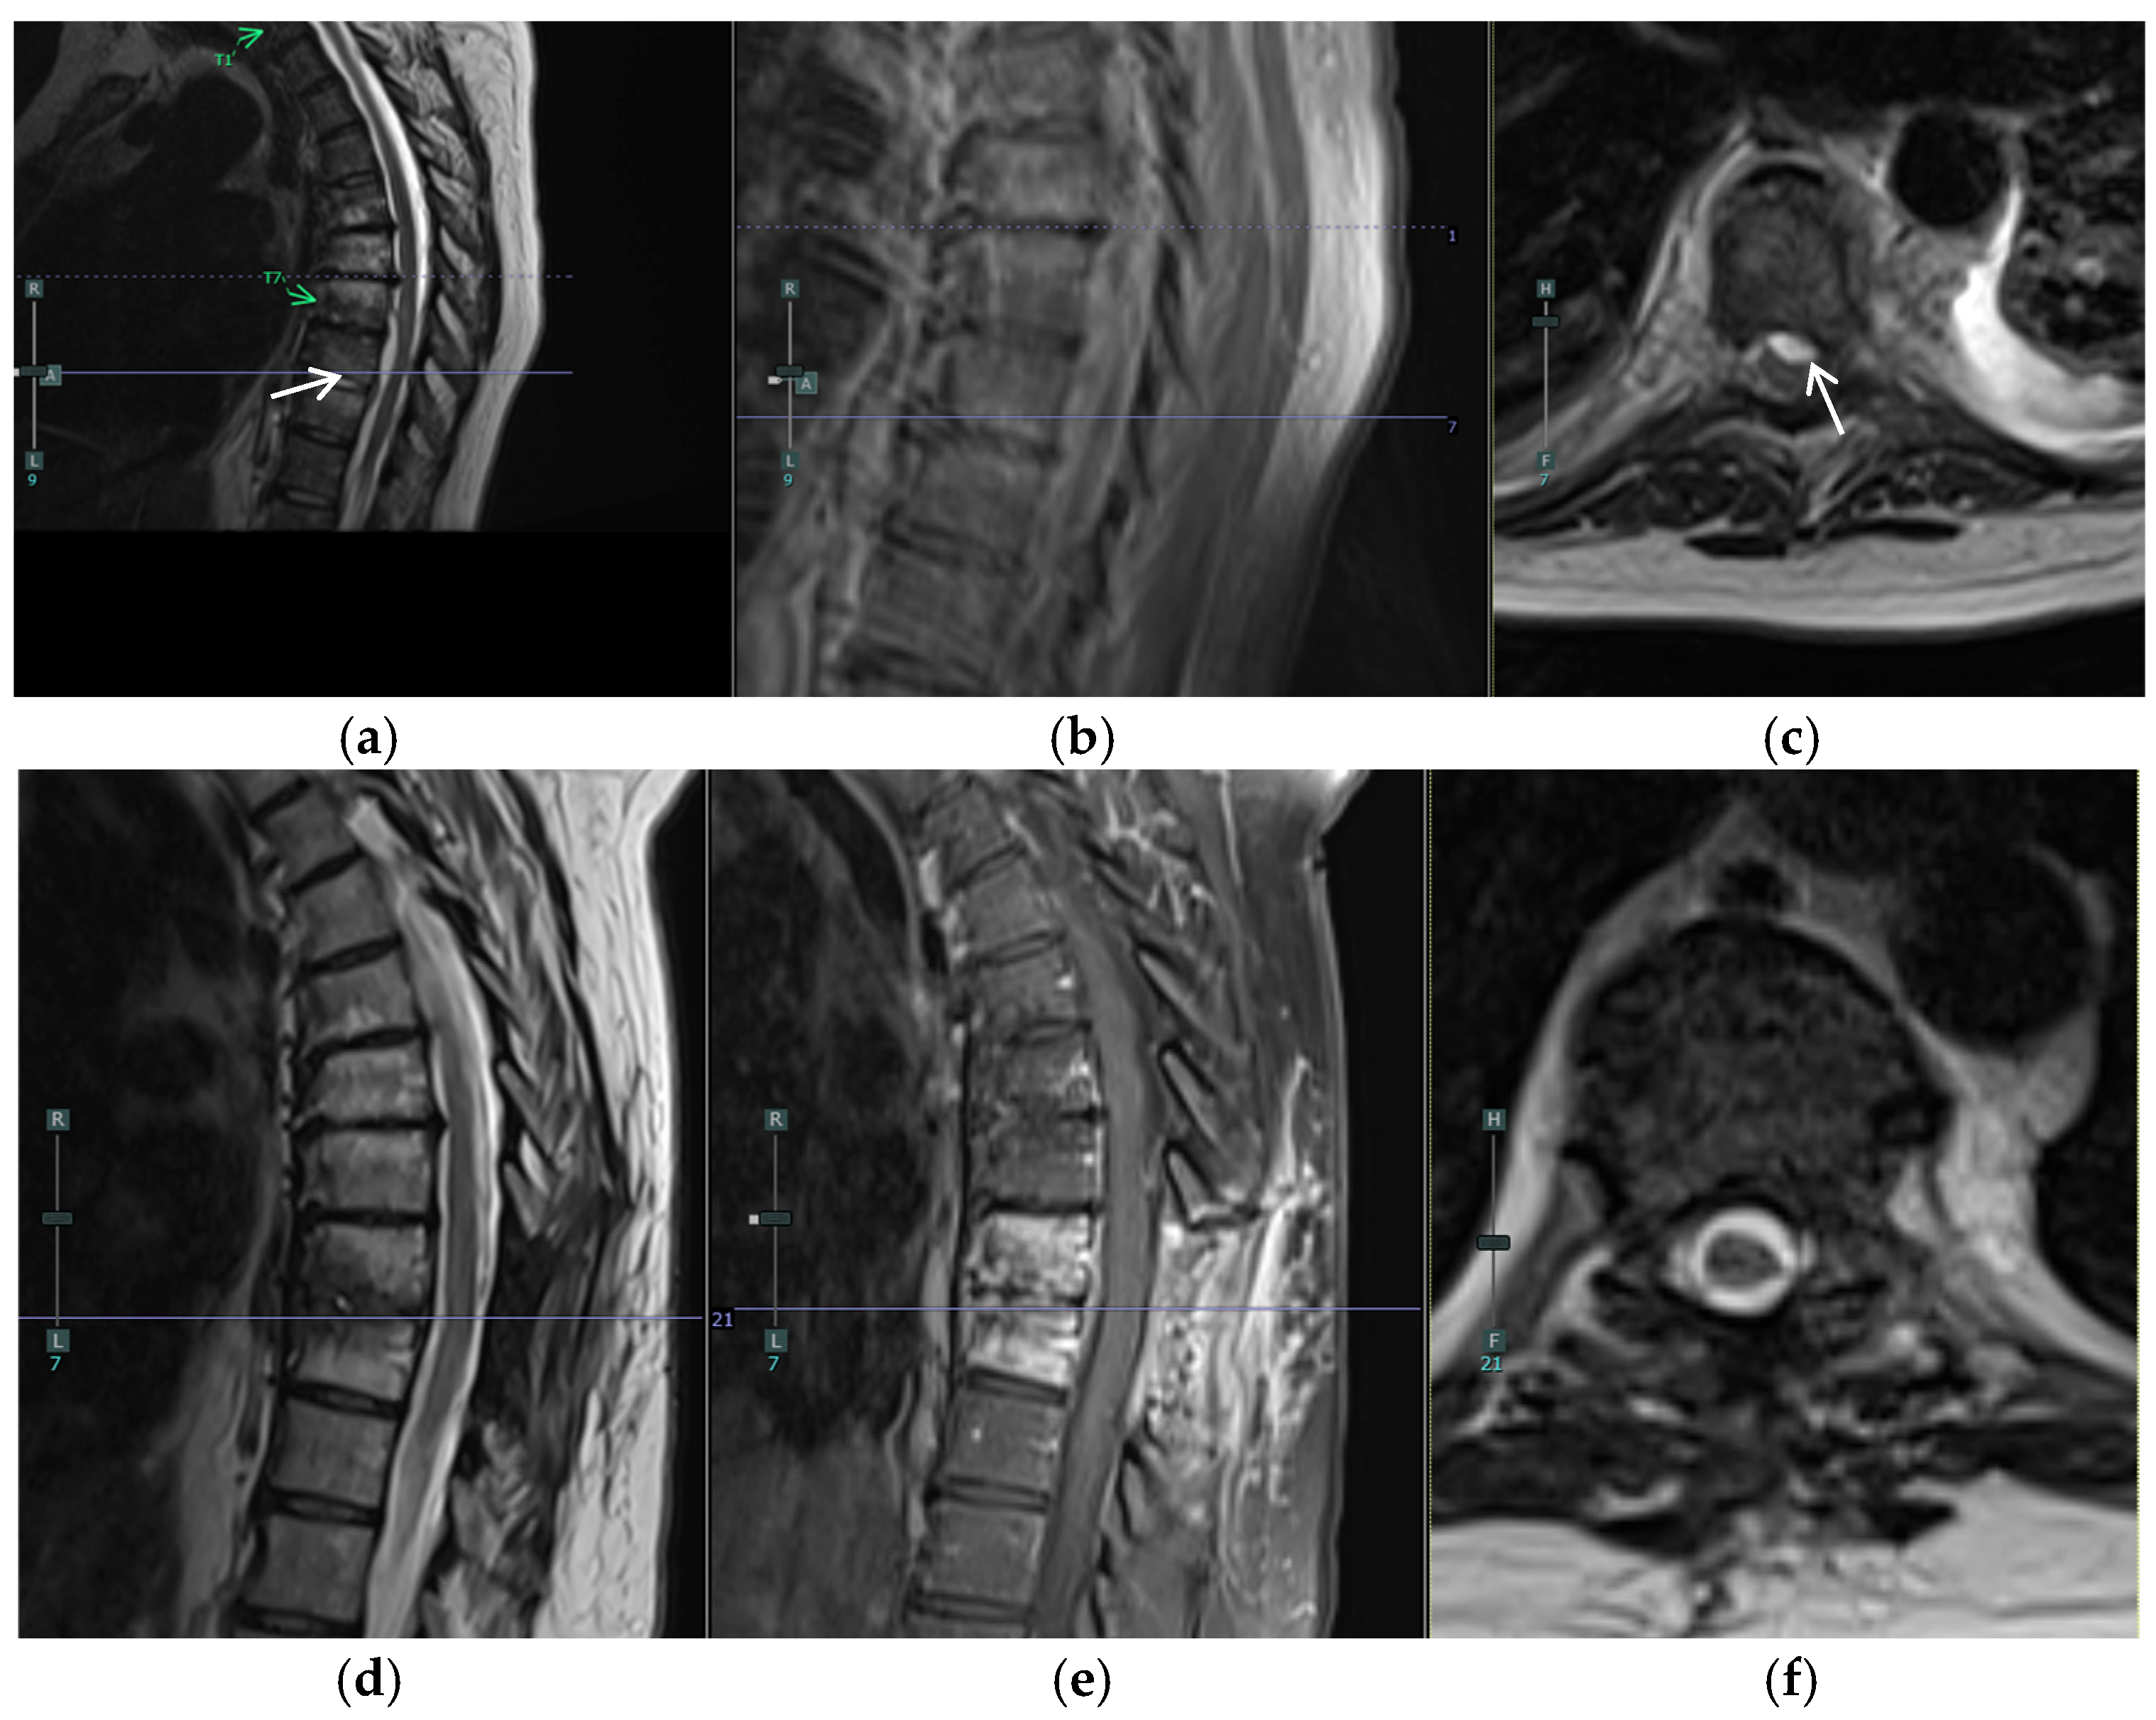

A 57-year-old female with a past medical history of osteoarthritis and prediabetes presented with three days of worsening back and left leg pain. Her initial examination revealed significant tenderness in the lumbar region and decreased sensation in the left S1 distribution. She had preserved motor function but reported progressive difficulty with ambulation due to pain. Two months prior, she had undergone a T8–T10 laminectomy for excision and drainage of a thoracic epidural abscess and left piriformis abscess aspiration, followed by a six-week course of intravenous antibiotics (Figure 1a–c). Imaging at presentation demonstrated a resolving thoracic infection but revealed worsening diffuse lumbar facet infection and a left-sided L5/S1 epidural abscess causing cauda equina and S1 root compression (Figure 1d–f and Figure 2).

Figure 1. (ac) MRI of the thoracic spine two months prior to operation prior to T8–T10 laminectomy for excision and drainage of a thoracic epidural abscess (white arrows) and left piriformis abscess aspiration: (a) Sagittal T2, (b) Sagittal T1 with contrast, and (c) Axial T2 at T8/T9. (df) Preoperative MRI of the thoracic spine, s/p original T8-T10 laminectomy, showing worsening diffuse lumbar facet infection and resolution of thoracic epidural abscess: (d) Sagittal T2, (e) Sagittal T1 with contrast, and (f) Axial T2 with contrast at T8/T9.